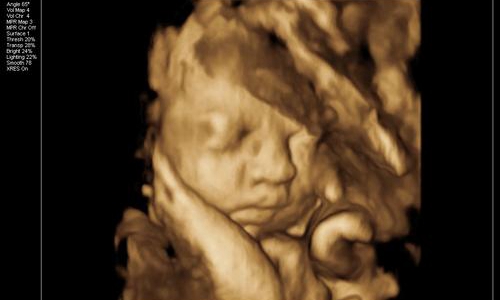

朋友28周的时候叫我陪着去体检,给宝宝照下四维彩照,看看胎儿生长发育过程中有没有变畸形。

因为宝宝在子宫内发育的非常好,活蹦乱跳的。半个小时,朋友拿着四维彩照的照片一言难尽。

这也太丑了吧!朋友说自己和老公的长相都不差,为什么生育的孩子确实塌鼻梁、大鼻孔、厚嘴唇呢?

那山根宽的像座独木桥,整个一阿凡达!欲哭无泪的朋友觉得打击太大,连着好几天都沉浸在悲伤中不能自拔。

胎儿的面部脂肪还没有完全堆积,因此从四维看到的脸蛋来说是比较丑的,类似于外星人。头部和身体的占比例大概是2:1,以成年人的视觉来看可不是怪异么。

再者,孕妇拍摄四维的目的,便是排除胎儿面部是否畸形。所以会根据声波成像技术来填充图像,再将口、鼻、眼等细节放大。

但是小宝宝的口耳鼻实在太细节,声波反弹较弱,因此连接到电脑上后会另外填充成像。毕竟四维彩照和我们平时拍照的像素不一样,它是由彩超探头采集到的数据以此合成一个大致的影像。

那么打印出来后自然模糊,边缘不清晰,导致小宝宝的五官和肢体看起来扭曲变形。一定程度上*化丑**了宝宝,让新手爸妈们怀疑人生。

所以,在探头勘测超声波影像时,胎儿在动。加上胎儿整个是泡在羊水里面,左动一下,右动一下,拍摄出来的成像难免会失真。

综上所述,四维彩照出来的胎儿成像,并不会是宝宝实际出生的样子。就和我们去一个餐厅吃饭一样,实物与图片不符。